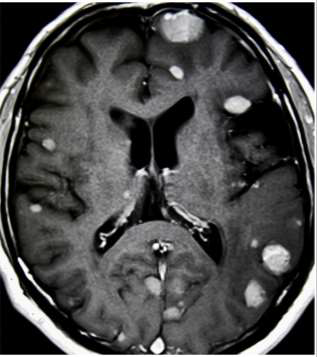

S.S.A, 50 anos, sexo masculino, procedente de Palmares-PE, vai ao ambulatório de neurocirurgia, encaminhado pela oncologia. Relata perda de peso (14Kg) e alguns episódios de crise convulsiva. É etilista e tabagista. Ao exame: consciente, orientado e com motricidade preservada. Trouxe imagens de RM do encéfalo com contraste.

Sobre as metástases cerebrais, assinale a alternativa INCORRETA.